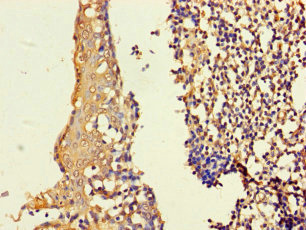

ApplicationELISA, WB, IHC; Recommended dilution: WB:1:1000-1:5000, IHC:1:20-1:200